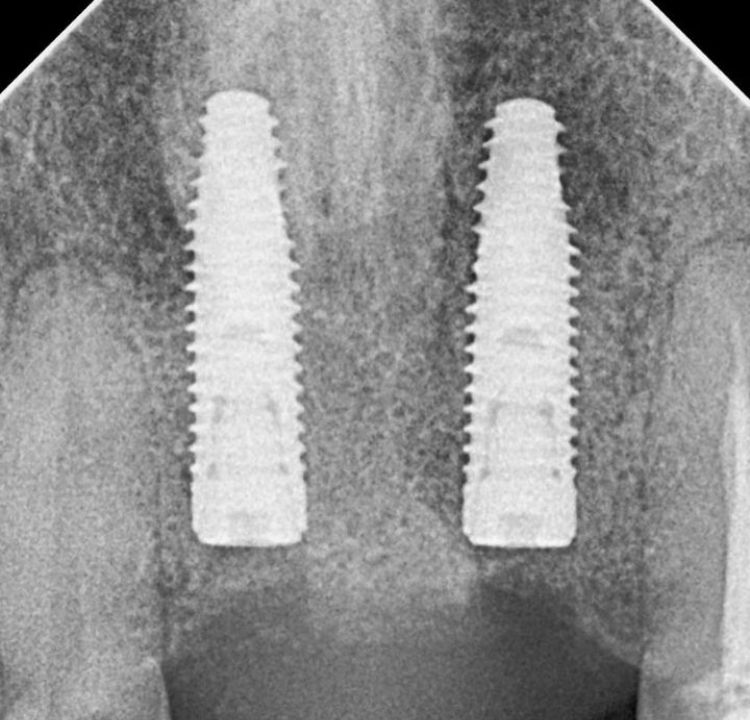

¿Que es un Implante Dental?

- Es un aditamento con forma de tornillo elaborado de titanio o de zirconio, que se inserta en el hueso a través de una pequeña cirugía, hasta que se osteointegre con el hueso y se coloque un provisional y posteriormente una corona definitiva.

-La ventaja de los Implantes Dentales es que sustituyen a los dientes o muelas perdidos sin que se tenga que desgastar los dientes adyacentes para un puente fijo.